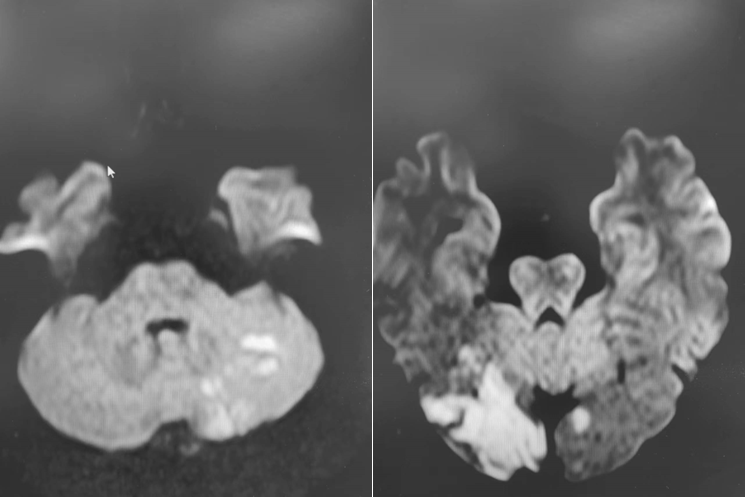

入院影像检查

术前造影:

导丝怎么扩【载药时代 球扩天下】NOVA DES®颅内药物洗脱支架在椎动脉颅内段重度狭窄的应用二例_https://www.jmylbn.com_新闻资讯_第18张

颅脑DWI+MRA:

导丝怎么扩【载药时代 球扩天下】NOVA DES®颅内药物洗脱支架在椎动脉颅内段重度狭窄的应用二例_https://www.jmylbn.com_新闻资讯_第20张

诊断

主要诊断:

1.右侧椎动脉V4段重度狭窄(90%);

2.高血压病2级 高危;

3.小脑梗死。